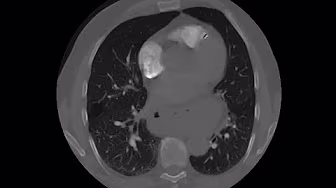

Today, I review, link to, and embed How to read a CTPA and diagnose a PE (CT pulmonary angiogram – pulmonary embolism) from Turkleton Radiology.

Jul 27, 2022CTPA is performed to evaluate for pulmonary embolism. This video is my approach in reading a CTPA.